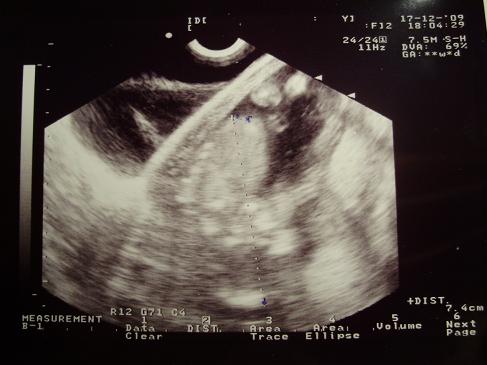

Właśnie wróciłam z Łodzi od gina brrr, ale mróz :-) u dzidziusia wszystko w porządku, ale niestety nie był zbyt ruchliwy, tylko trochę machał rączkami i nóżkami :-) dołączam usg, ale nie wiem czy ktoś się czegoś dopatrzy, bo ja przyznam, że ciężko mi to wyszło :-D

• PC170045.JPG

PC170045.JPG

38,1 KB · Wyświetleń: 90